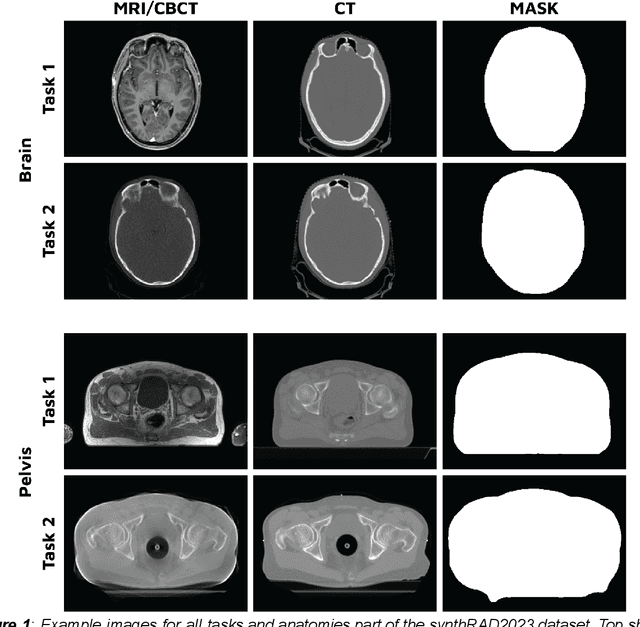

Abstract:Purpose: Medical imaging has become increasingly important in diagnosing and treating oncological patients, particularly in radiotherapy. Recent advances in synthetic computed tomography (sCT) generation have increased interest in public challenges to provide data and evaluation metrics for comparing different approaches openly. This paper describes a dataset of brain and pelvis computed tomography (CT) images with rigidly registered CBCT and MRI images to facilitate the development and evaluation of sCT generation for radiotherapy planning. Acquisition and validation methods: The dataset consists of CT, CBCT, and MRI of 540 brains and 540 pelvic radiotherapy patients from three Dutch university medical centers. Subjects' ages ranged from 3 to 93 years, with a mean age of 60. Various scanner models and acquisition settings were used across patients from the three data-providing centers. Details are available in CSV files provided with the datasets. Data format and usage notes: The data is available on Zenodo (https://doi.org/10.5281/zenodo.7260705) under the SynthRAD2023 collection. The images for each subject are available in nifti format. Potential applications: This dataset will enable the evaluation and development of image synthesis algorithms for radiotherapy purposes on a realistic multi-center dataset with varying acquisition protocols. Synthetic CT generation has numerous applications in radiation therapy, including diagnosis, treatment planning, treatment monitoring, and surgical planning.